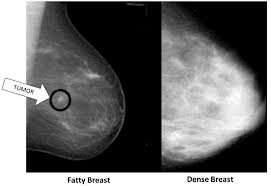

The mass is hypoechoic with posterior shadowing (orange arrow), taller than wide and moderate vascularity. This breast cancer ultrasound image shows changes related to breast cancer that are not seen as microcalcifications or a mass or lump. Other ultrasound findings that suggest breast cancer include: Depending on your symptoms, your doctor makes a diagnosis based on a combination of tests and procedures. This can make it harder for your radiologist to spot signs of breast cancer, since dense tissue and tumors both look white in mammogram images.

Breast ultrasound images are seen from superficial (skin) to deep (chest wall muscle) over a segment of tissue. Other ultrasound findings that suggest breast cancer include: Looks larger, thicker or heavier. Other ultrasound findings that suggest breast cancer include: Presenting radiologic appearance of breast dcis microcalcifications at breast cancer screening we can see from the chart above that overall, the most commonly occuring mammographic indication of dcis are the crushed stone microcalcifications. This can make it harder for your radiologist to spot signs of breast cancer, since dense tissue and tumors both look white in mammogram images. While it may look like a fuzzy, spotty television screen with different shades of grey to a patient, the ultrasound technician and the radiologist use these images to diagnose masses and tumors. Any area that does not look like normal tissue is a possible cause for concern.

Rather, the right breast is seen as smaller than the left breast. The sound waves pass through the breast and bounce back or echo from various tissues to form a picture of the internal structures of the breast. Inflammatory breast cancer pictures and symptoms. Papillary dcis, a special variant, will show up as matter within the ducts, like a clog within a pipe. Breast cancer is among the most common causes of cancer deaths today, coming fifth after lung, stomach, liver and colon cancers. A mammogram image has a black background and shows the breast in variations of gray and white. But radiologists can still see signs of cancer. During a breast exam, your doctor looks for visual changes and uses their fingers to feel.